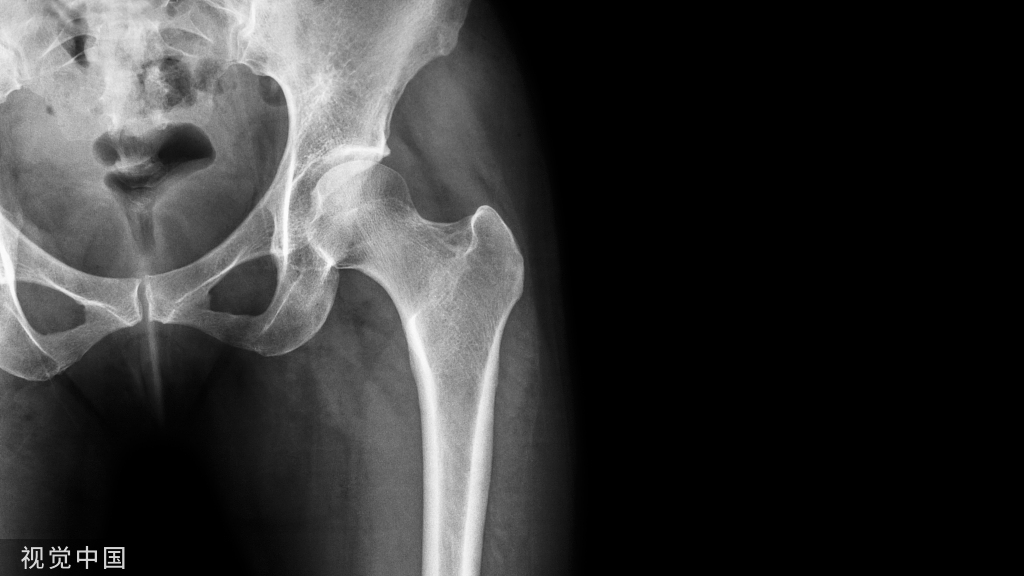

老年股骨颈骨折的双动臼杯置入技巧!

根据术前模板测量来选择内植物的尺寸。术前模板测量可以帮助确定髋臼的旋转中心位置、臼杯的大小和方位。下面介绍Captiv和Captiole™ Evolutis双动臼杯的置入。

双动臼杯可以通过任何传统的手术入路进行置入。如图3所示手术入路,髋关节由后侧入路暴露。暴露髋部骨折部位并且切除股骨头。